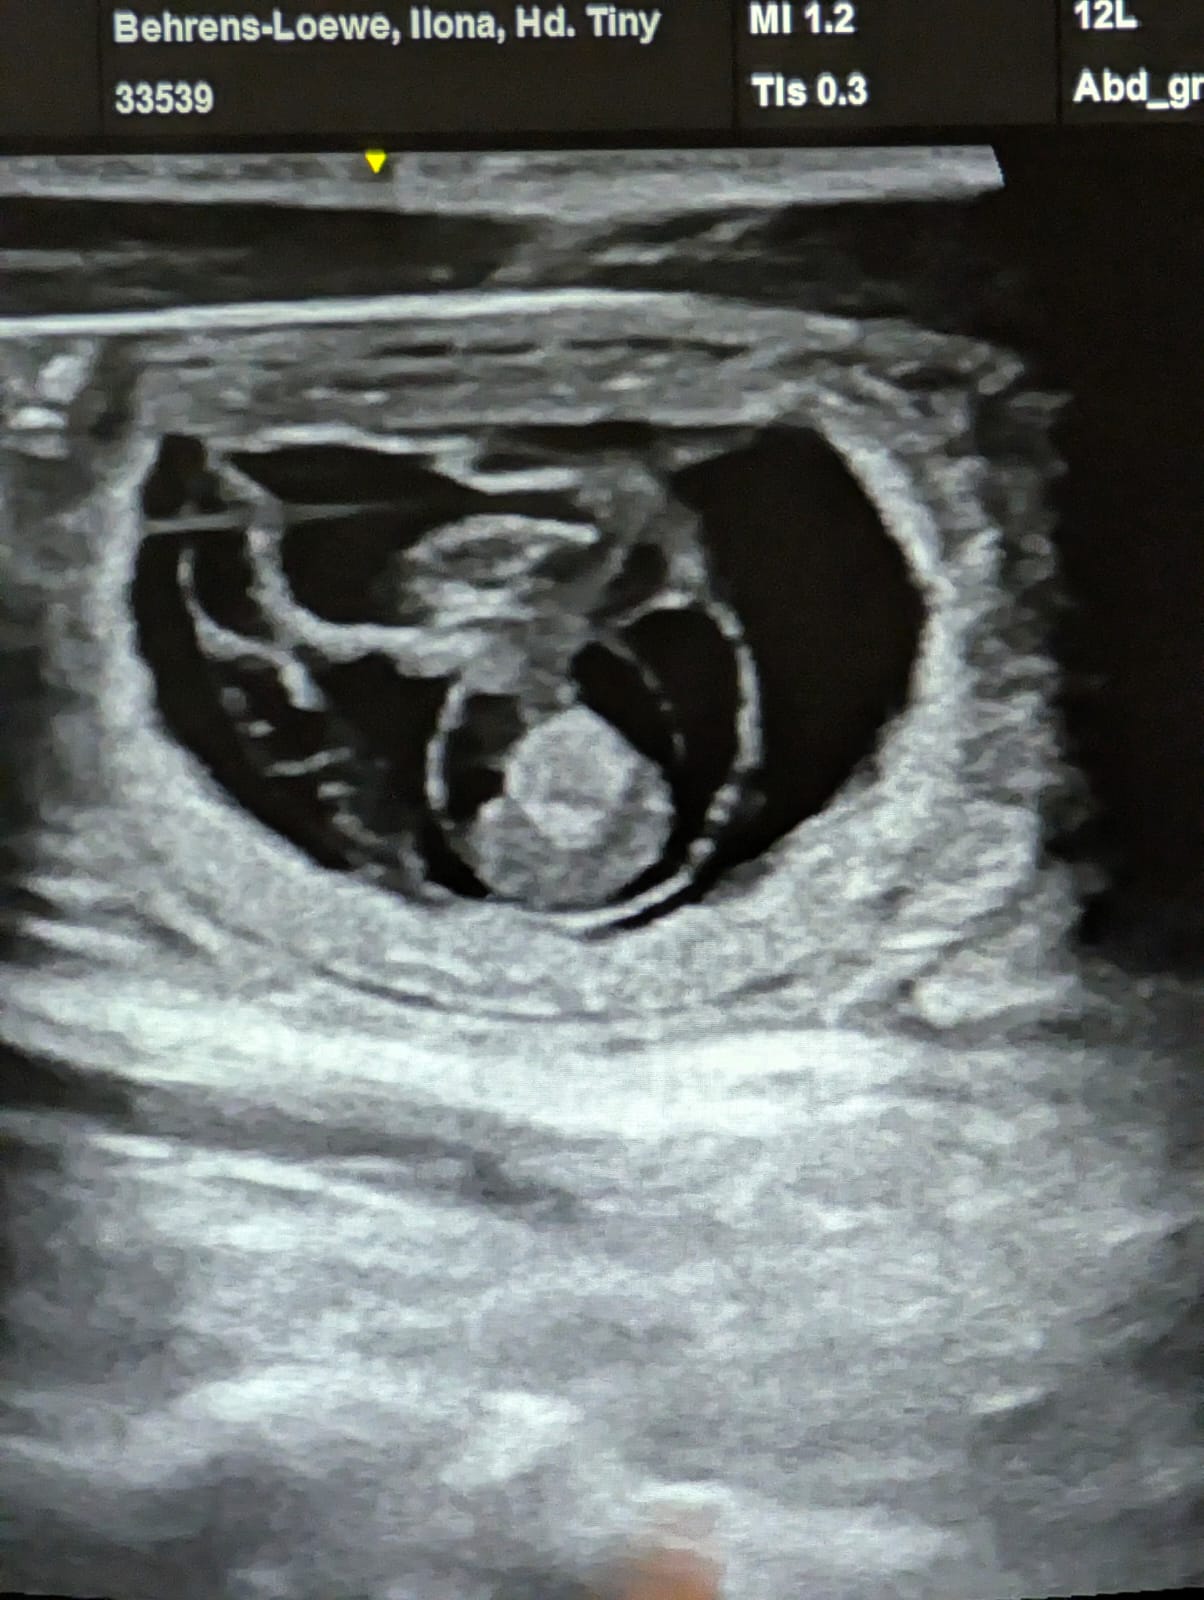

🥰 Wunderschöne Nachrichten 🥰

Geburtstermin Ende März

Neuigkeiten von Culann's Amor

Stammbaum Vorschau vom Culann's E Wurf

Freudige Nachrichten !!!

Culann's Amor und Culann's Bahira haben eine schöne Zeit miteinander verbracht ....

Weitere Informationen zu gegebener Zeit - also bleibt gespannt !